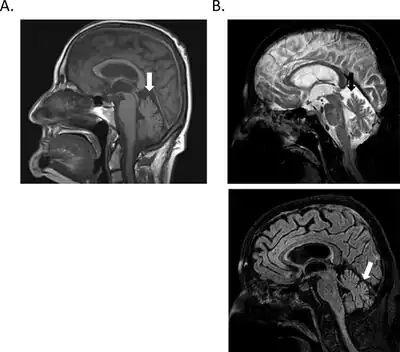

| a-c) Staining of human Purkinje cells with CDR2 and CDR2L antibodies | |